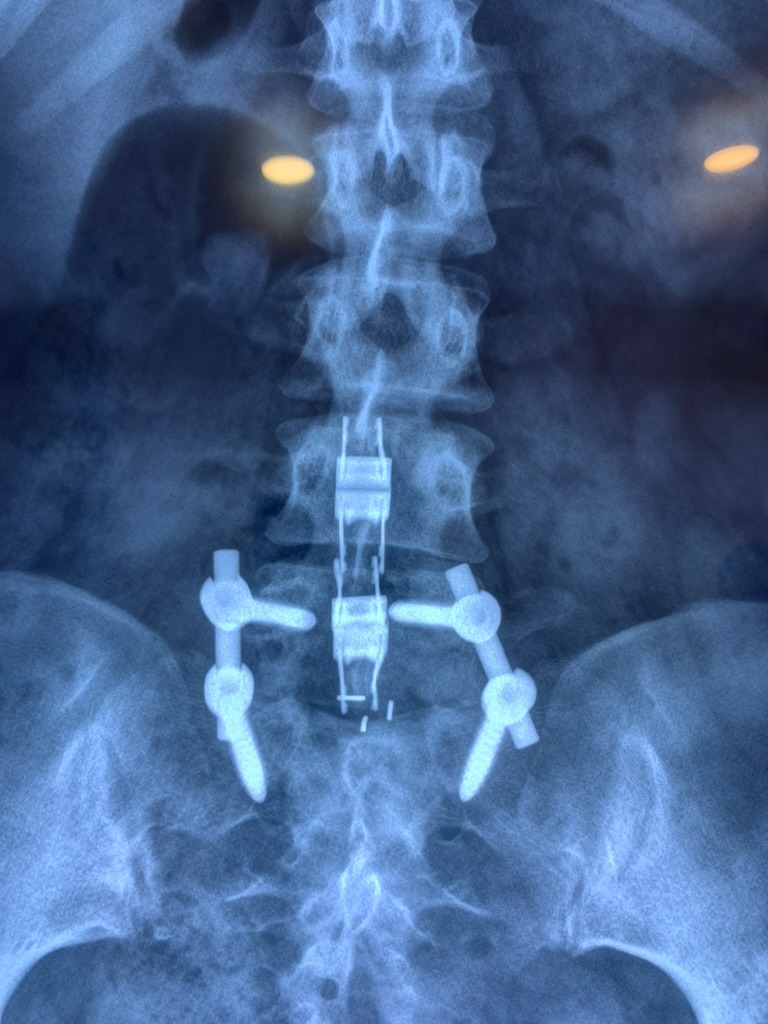

SURGERIES

RESULTS